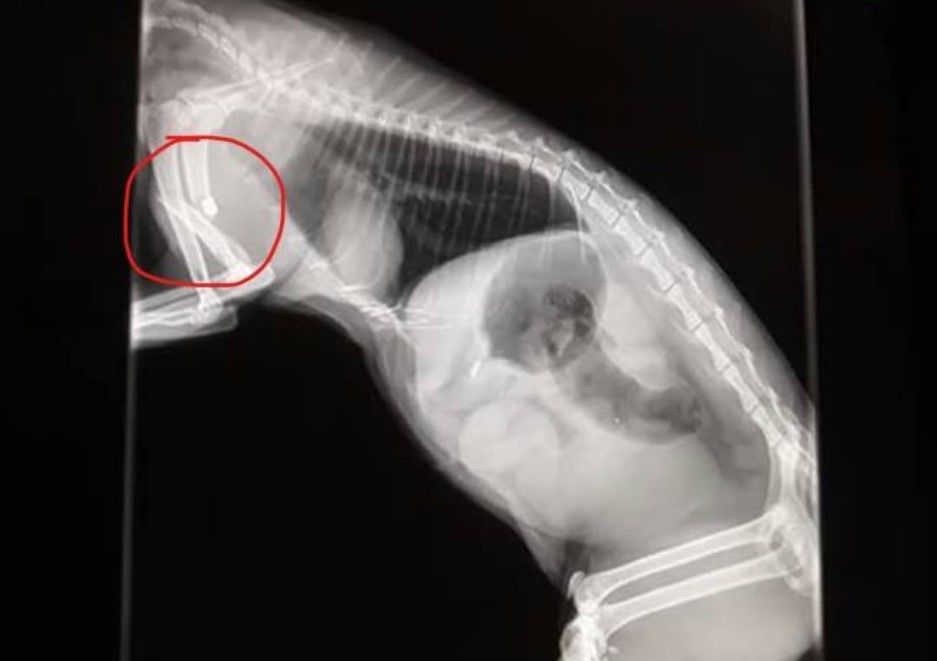

Την προσοχή των κατοίκων της οδού Βερμίου στην περιοχή της Αγίας Μαρίνας στην Ηλιούπολη Αττικής εφιστά η Ζ.Ε.Η. καθώς μια ακόμα γάτα που πυροβολήθηκε με αεροβόλο εκεί τελικά υπέκυψε στα τραύματα της καθώς το σφαιρίδιο του αεροβόλου όχι μόνο έσπασε το οστό του ποδιού της αλλά χτύπησε και τον πνεύμονα με αποτέλεσμα το ζώο τελικά να πεθάνει. Το ζώο βρήκε πυροβολημένο στις 19 Ιουλίου κάτοικος της περιοχής και το μετέφερε σε κτηνιατρείο όπου και διαπιστώθηκε από την ακτινογραφία τι είχε.

Γνωρίζουμε πως η ντροπή του ανθρώπινου γένους που την πυροβόλησε πιθανόν να χαρεί αν μάθει ότι της έδωσε ένα πολύ επώδυνο κι αγωνιώδες τέλος, αφού το βλήμα προκάλεσε συντριπτικό κάταγμα στο μπροστινό της πόδι και της χτύπησε τον πνεύμονα, τόσο όσο χρειαζόταν για να περάσει τις τελευταίες της μέρες παλεύοντας για μια ανάσα παρά τις προσπάθειες των γιατρών που τη μεταφέραμε.